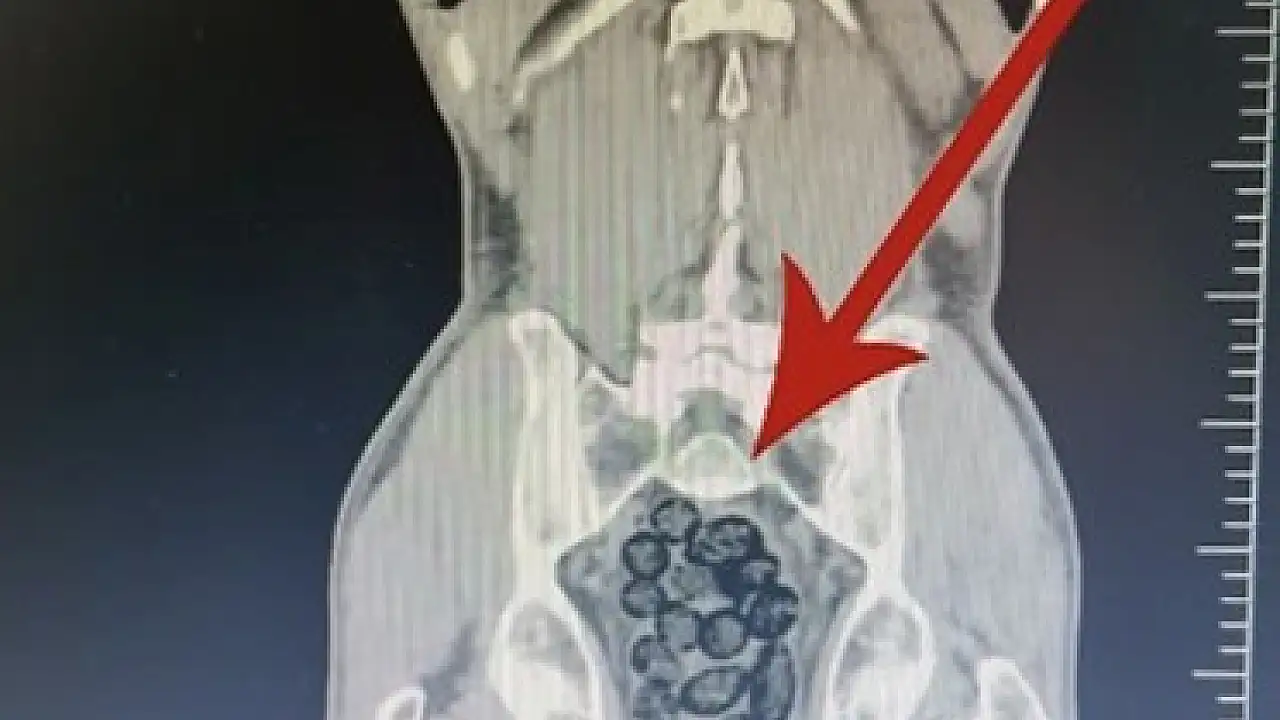

Yapılan tıbbi kontroller sonucunda yabancı uyruklu şahsın midesinde 64 parça halinde paketlenmiş uyuşturucu madde bulunduğu belirlendi. Ele geçirilen maddenin toplam 472 gram metamfetamin olduğu tespit edildi.

Gözaltına alınan şüphelinin midesindeki uyuşturucu maddeler sağlık ekipleri tarafından çıkarıldı. Emniyetteki işlemleri tamamlanan şahıs, adliyeye sevk edildi. Mahkemeye çıkarılan zanlı, tutuklanarak cezaevine gönderildi.